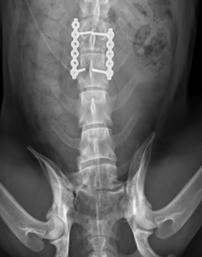

“When Monty came in, he had a number of injuries and was obviously in a lot of discomfort,” said Surgical Clinician, Rhys Treharne. “We did CT and MRI scans to work out what was wrong, and they pinpointed a fracture to his spine and also a tendon rupture to his pelvis.

“If we hadn’t operated the fracture could have got much worse, so we went ahead with surgery and put in plates with screws to repair it. A few days later we carried out another surgery to fix the rupture."